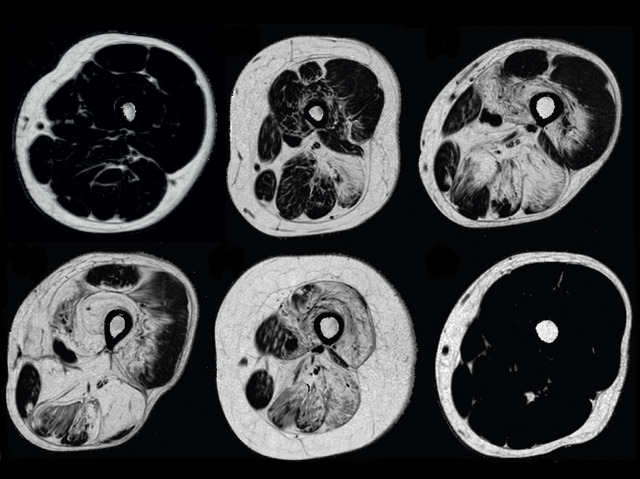

Muscle Magnets

The muscular dystrophies (MDs) affect the lives of around 70,000 people in the UK, causing progressive muscle weakening and sometimes early death. These cross-sections of the thighs of patients with limb girdle muscular dystrophy (LGMD), which mostly affects the leg and arm muscles, were made using magnetic resonance imaging (MRI). Bottom right is muscle from a healthy person, while the others are from LGMD sufferers at various stages. As the condition progresses, muscle (dark areas) is replaced by fat (paler areas). Analysing these images revealed which particular muscles are affected and when, and how the disease differs in men and women. MDs are currently incurable, Duchenne being one of the most severe; this information will therefore help doctors assess a patient’s condition, and their reaction to potential treatments. Biopsies and walking checks, which are currently used, are more invasive and effortful, so MRI will also be more convenient for patients.